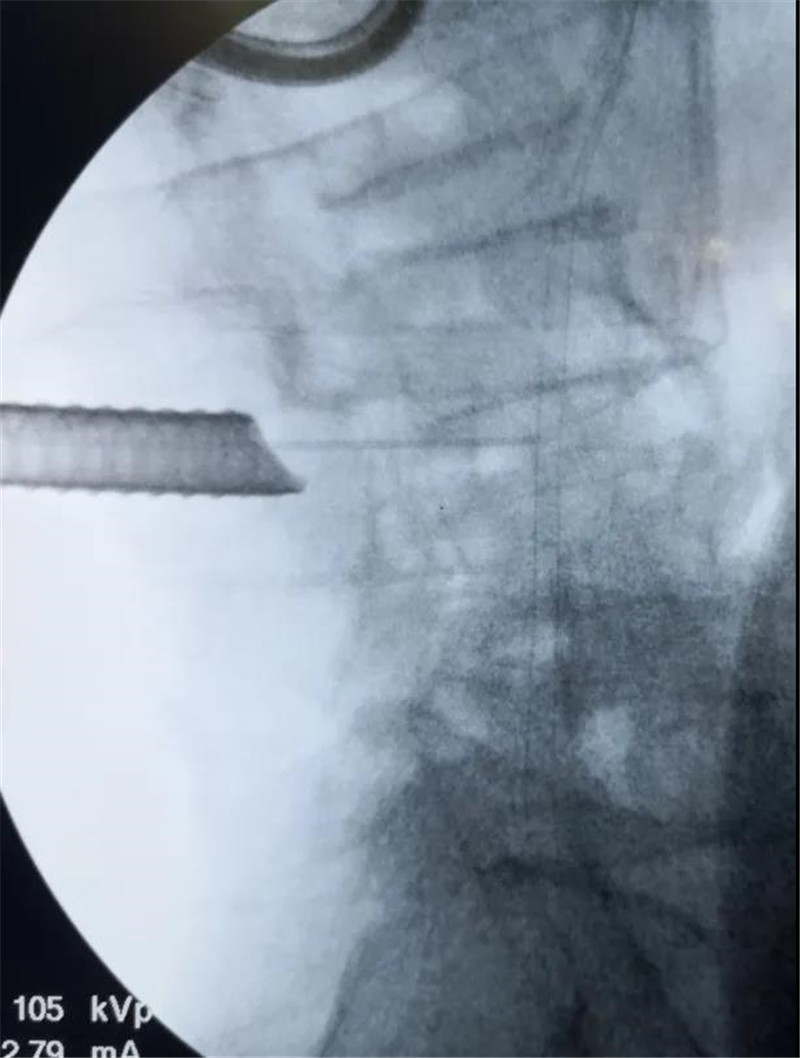

来到三水区人民医院后,医生为他做了系统全面的检查,发现赵伯除了胃出血外,腰椎间盘突出严重,已经压迫到神经,导致他出现腿麻腿痛的现象。消化内科住院10天调理好胃之后,在脊柱关节外科潘磊主任的指导下,由薛厚军副主任医师主刀,黄杰彬医师一助顺利为赵伯实施了微创腰椎间盘摘除及神经松解手术,术后两天,赵伯即可下地行走。

椎间盘巨大突出,右侧神经受压

本次赵伯的手术就是采用最新引进的德国Delta大通道脊柱内镜系统,手术非常顺利,术后病人感觉也很好。“Delta内镜系统是在孔镜基础上发展起来的,它弥补了孔镜的一些不足,对于一些特殊的颈椎间盘突出、腰椎间盘突出、腰椎管狭窄症患者操作更简便,同时又具有创伤小、出血少、术后功能恢复快、感染率低等优点,对老年性椎管狭窄等患者优势更明显。”黄杰彬医师说。